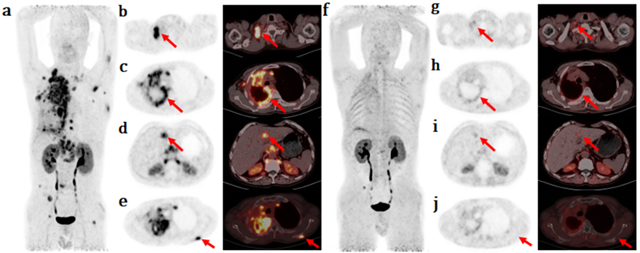

近期,西南医科大学附属中医医院老年病科收治了多例中高龄肺部感染的患者,其中多名患者无发热、无咳嗽症状,但经检查后,均已出现严重肺部感染。CASE 166岁的老赵,因感冒自己在家服用抗病毒颗粒1次,自认为已痊愈,于是停药,不曾想一周后出现气促...